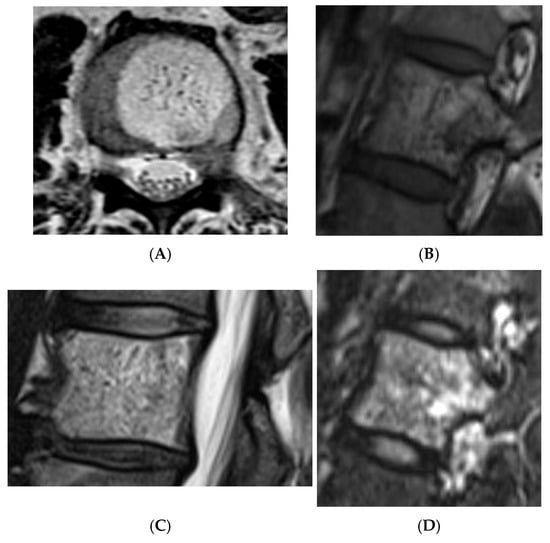

Collision lesions of the spine are rare, with few documented cases involving the spinal cord. Notably, metastases from renal cell carcinoma to spinal hemangioblastomas in patients with Von Hippel–Lindau syndrome have been reported [21]. However, collision lesions specifically involving vertebral haemangiomas are exceedingly uncommon, with only a few cases of metastatic infiltration into haemangiomas described in the literature. These include metastases from renal cell carcinoma [22,23], colonic adenocarcinoma [24], and lymphoma [25], each leading to varying clinical manifestations, including spinal cord compression [25] (Figure 14, Figure 15 and Figure 16).

Figure 14.

Collision Lesions: Typical and atypical haemangioma of vertebral body. (A) Axial T1W MRI demonstrating a classic haemangioma with a T1 hyperintense lesion occupying the vertebral body, with a smaller atypical T1 hypointense lesion (circled) adjacent, in keeping with an atypical haemangioma. (B) Axial T2W MRI with the same lesions—the atypical lesion to the left side of the patient (vertebral body) has a higher vascular component and therefore is more hyperintense than the adjacent and larger typical haemangioma. The larger lesion still remains hyperintense on T2, in keeping with predominant internal fat content. (C) Sagittal T1W spine MRI. (D) Sagittal T2W spine MRI. (E) Sagittal STIR spine MRI demonstrating fat suppression within the typical haemangioma with hyperintense signal within the atypical haemangioma as a collision lesion example.

Figure 15.

Collision Lesions: Renal cell carcinoma metastases within a haemangioma of vertebral body, Case 1. (A) Axial T1W MRI—A large T1 hyperintense lesion with typical appearances of a haemangioma within the vertebral body, associated with a smaller peripheral located T1 isointense lesion with extraosseous component (circled). (B) Axial T2W MRI—Same case with T2 hyperintense vertebral body lesion confirming internal fat content and the eccentrically located T2 hyper- to isointense lesion proven to be a renal cell carcinoma on histology.

Figure 16.

Collision Lesions—Renal cell carcinoma metastases within a haemangioma of the vertebral body, Case 2. (A) Axial T1W MRI with a typical vertebral body haemangioma with an abnormal low T1 signal in its posterolateral aspect with periosteal change (circled). (B) Axial T2W MRI demonstrates the aggressive lesion within and adjacent to the typical haemangioma in image (A). (C) Sagittal STIR MRI—Fat-suppressed haemangioma with a hyperintense (biopsy-proven) metastases in its posterior aspect involving the pedicle.

In a comprehensive case series, collision lesions with both typical and atypical haemangioma components as well as focal marrow hyperplasia were described [23]. A potential explanation for the latter phenomenon may lie in the histological subtype of vertebral haemangiomas; i.e., the capillary type contains intervening normal bone tissue, which may support hematopoietic proliferation, unlike the cavernous variant. This suggests that in rare cases, capillary-type osseous haemangiomas may serve as a substrate for focal marrow hyperplasia [23].